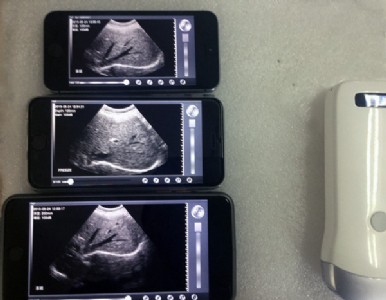

uprobe是一個陣列“探頭”(探頭式b超),只需這個“探頭”,并在智能終端(包括平板電腦和手機)上安 裝超聲軟件,就可實現b超的功能。

產品小巧便于攜帶,且和電腦、手機是無線連接,使用非常方便。

-會診功能:直接通過手機、平板實現互聯網遠程會診,也支持現場多部手機/平板同屏顯示進行會診 線陣系列技術指標:-掃描方式:電子陣列掃描 -探頭頻率:7.5mhz、10mhz兩種探頭-掃描深度:7.5mhz探頭為40mm~100mm,10mhz探頭為20~50mm,可調-顯示模式:b、b/m-圖像調節:增益、焦點、反相脈沖諧波、降噪-電池工作時間:3小時-充電方式:無線充電-測量功能:距離、面積、周長、心率、產科-尺寸:156mm×60mm×20mm-重量:250g-探頭與主機連接方式:wifi無線連接-wifi類型:802.11g/20mhz/2.4g/54mbps-軟件支持系統:蘋果apple macosx和安 卓android-圖像幀頻:12f/s-會診功能:直接通過手機、平板實現互聯網遠程會診,也支持現場多部手機/平板同屏顯示進行會診 產品配置: